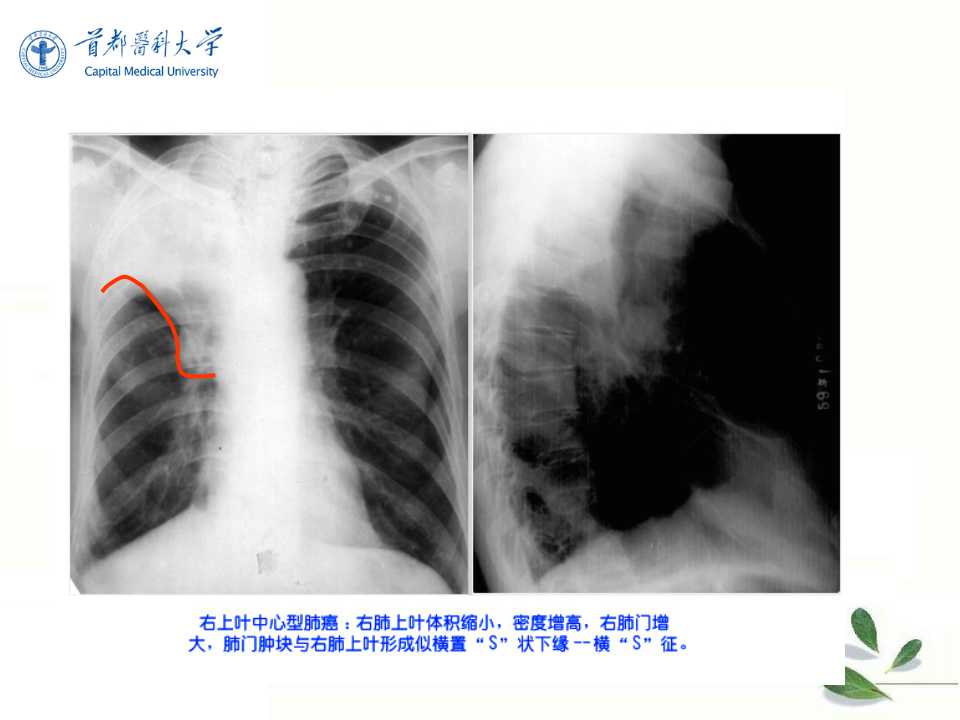

肺癌的影像学检查